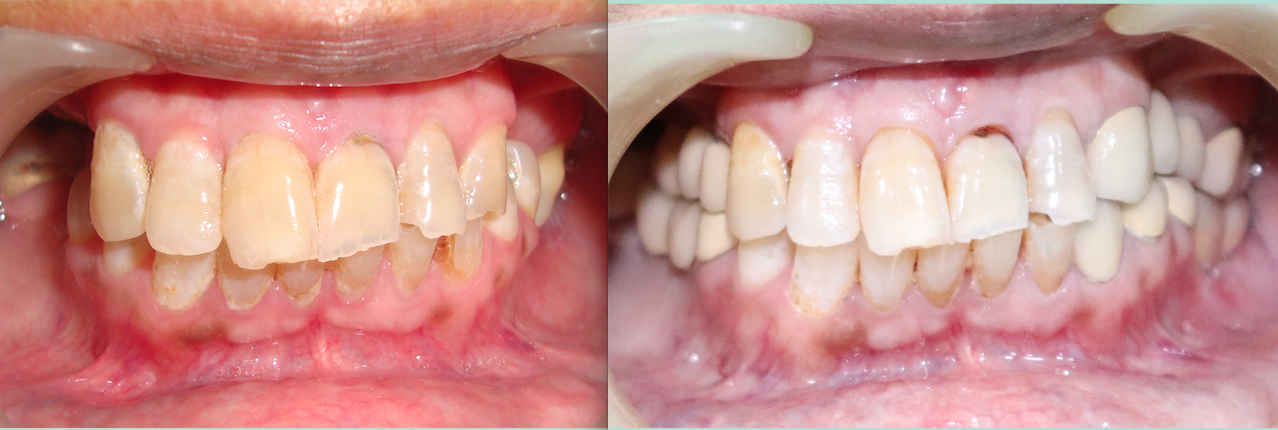

Full Mouth Rehabilitation

Card image